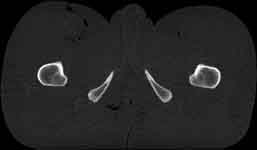

Visible Human male: Sectio transversalis 1940

CT

NMR

Pd                          / T2 \                         T1